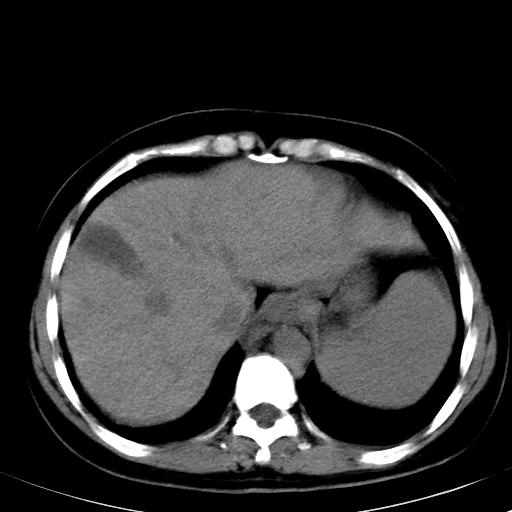

标题: CT19818:女40,脾大伴贫血,无肝炎病史 [打印本页]

标题: CT19818:女40,脾大伴贫血,无肝炎病史

肝各叶比例失调,肝裂增宽,支持肝硬化\\脾大.

左肝大/右肝小,脾大,考虑肝硬化门脉高压,脾大。  不知是否有血吸虫感染病史

肝叶比例失调,肝左叶明显增大,包膜欠规整,脾大,支持考虑肝硬化、门脉高压、脾大。